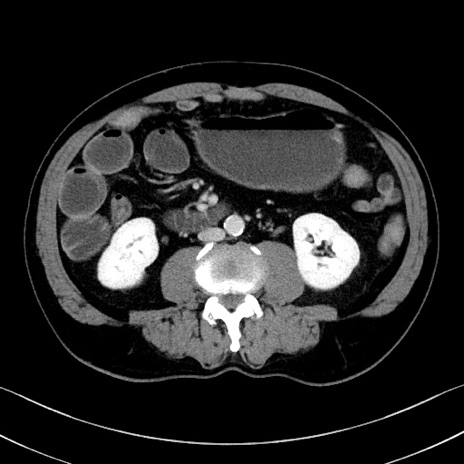

症例35(横断像)

【症例】70歳代 男性

【主訴】腹部膨満、嘔吐

【現病歴】昨日より腹部膨満感出現。本日増悪し、仙痛出現。嘔吐あり、受診。

【既往歴】糖尿病、胆摘後

【身体所見】BP 149/80mmHg、HR 74/min、BT 35.9℃、腹部:膨満、軟、圧痛なし。腸雑音減弱あり。上腹部正中切開瘢痕あり。

【データ】WBC 13500、CRP 1.72